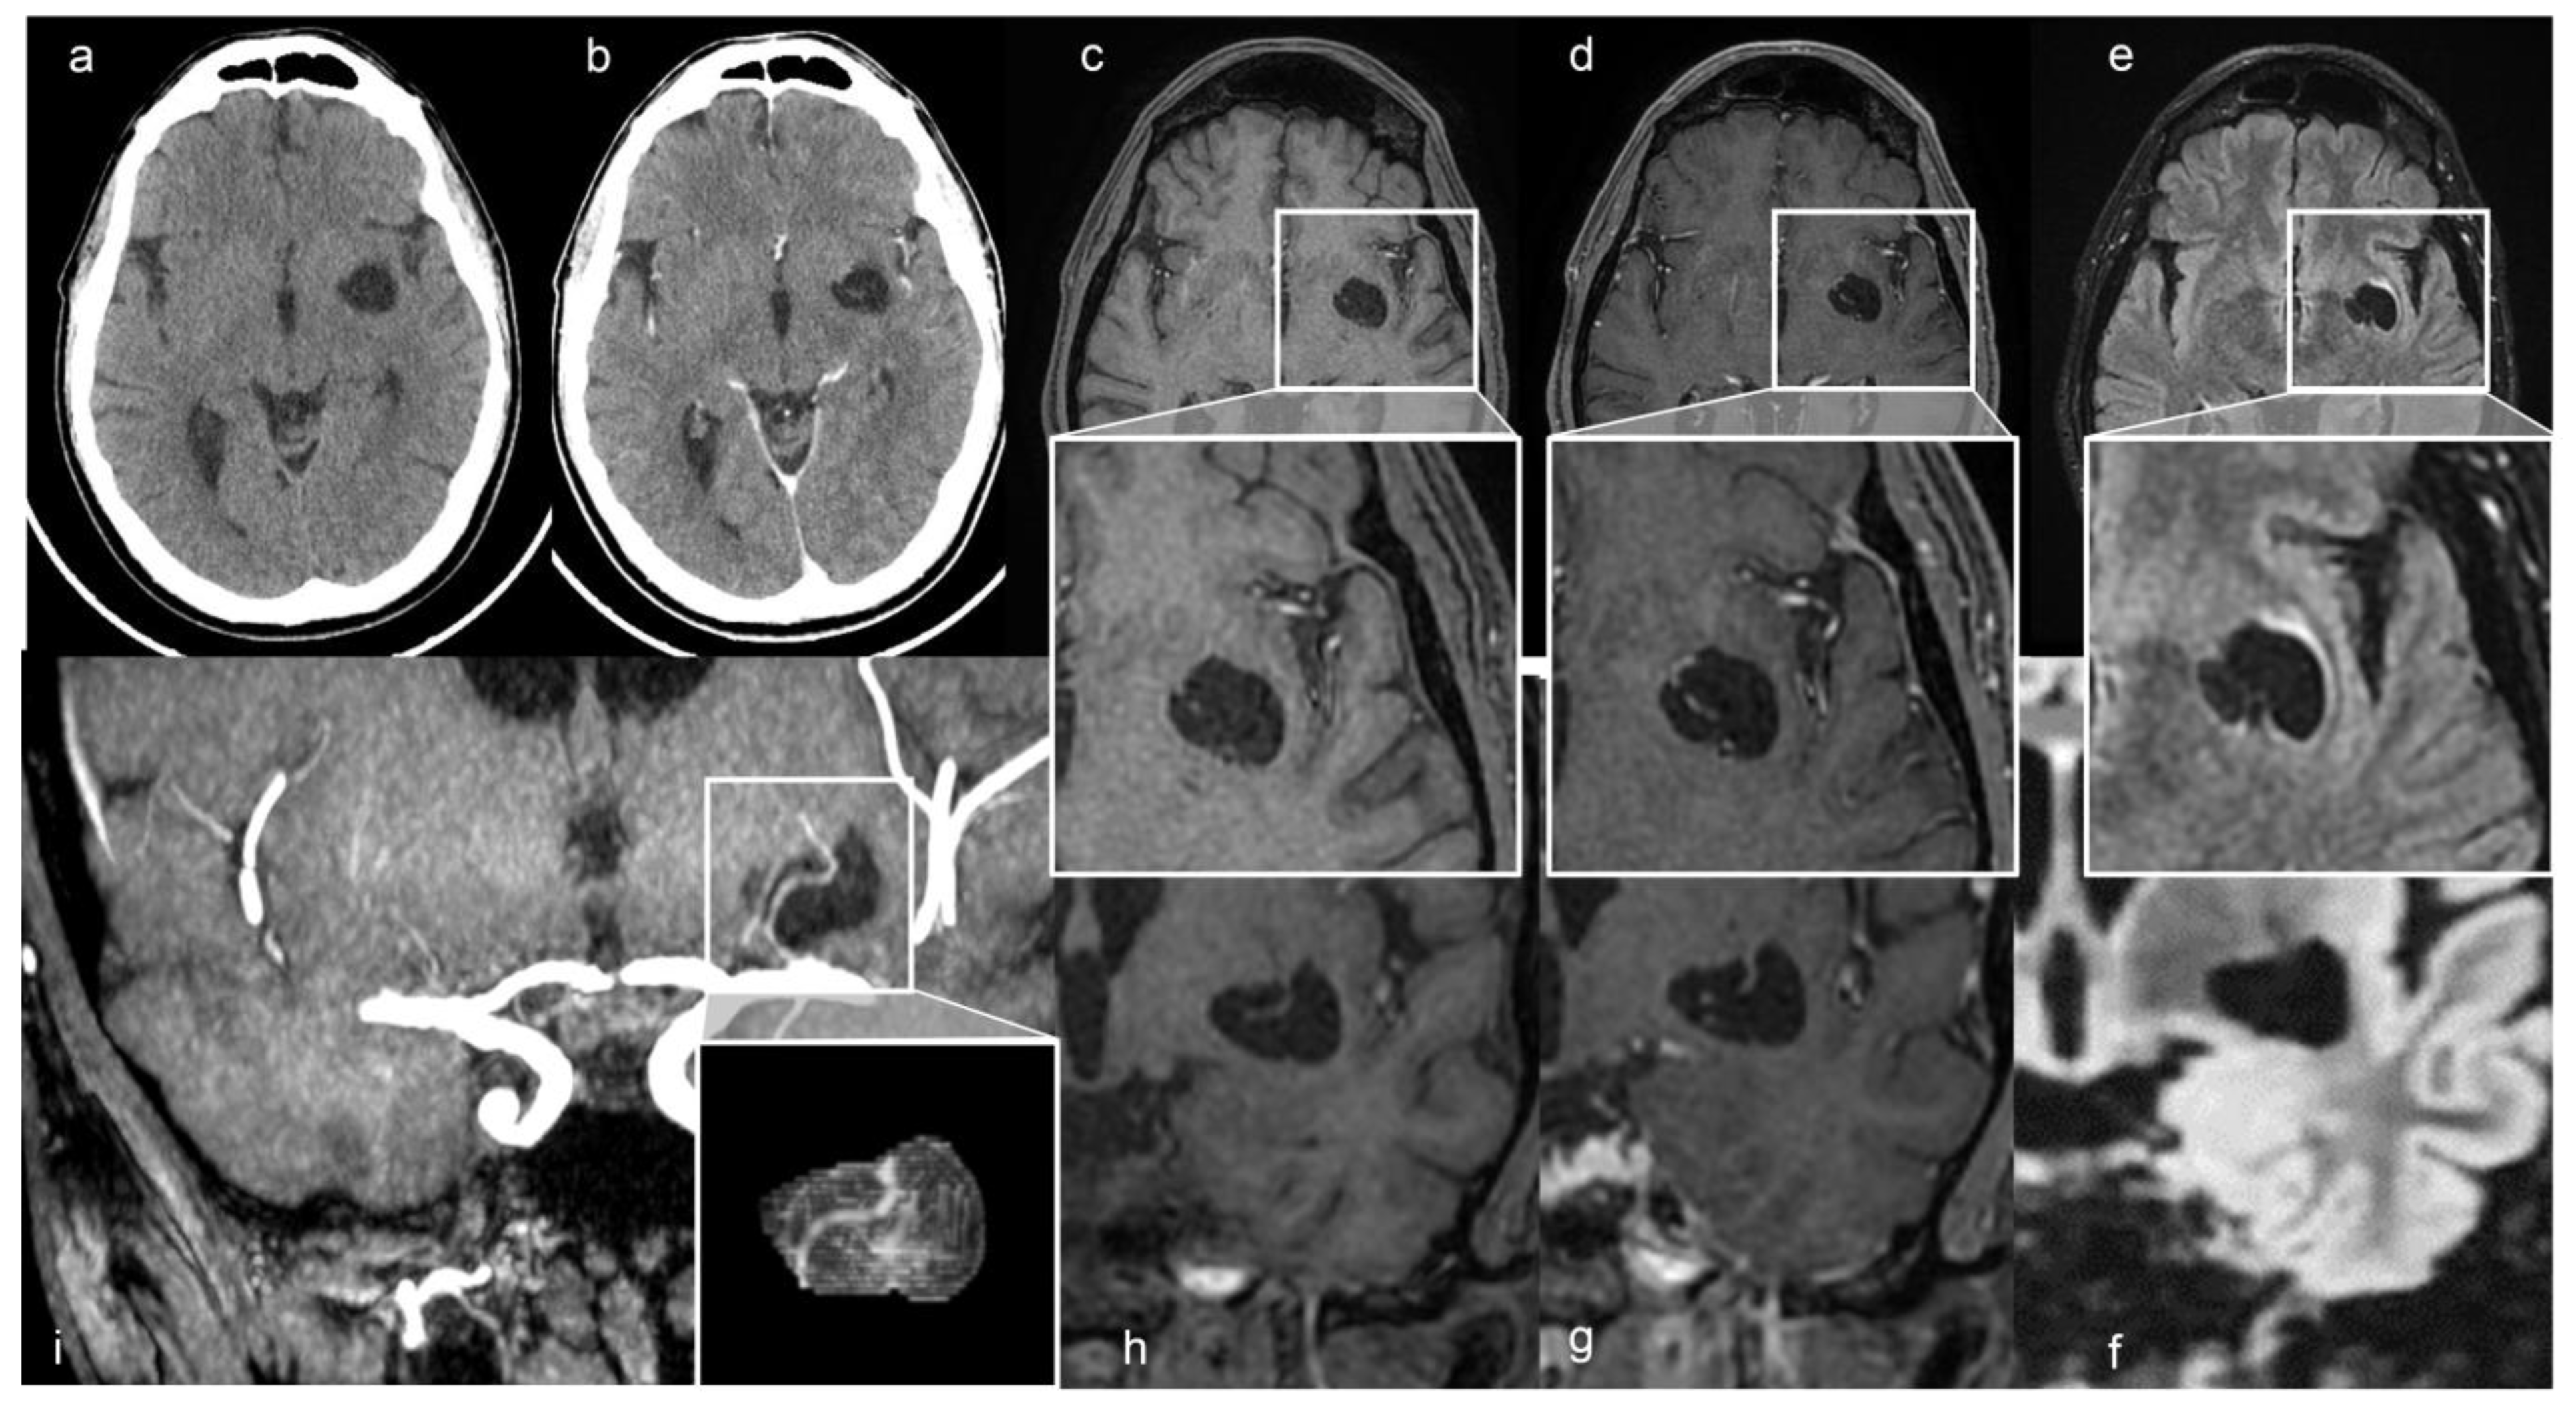

A 48-year-old man presented with a one-year history of diabetes mellitus (DM) type 1, diabetic polyuria, and polydipsia. Two months earlier, he had a fever (40 °C) for many days, partially resolved with broad-spectrum antibiotic therapy. One week later, he developed acute urinary retention. The abdominal ultrasound study showed up portal vein thrombosis and prostatic hypertrophy with calcifications. The Computed Tomography (CT) study of the abdomen showed a fluid/superfluid collection in the paramesocolic groove, extending caudally, reaching the recto-vesical cavity, where it appears partially organized. From the spleen-mesenteric confluence to the hepatic hilum, the vena porta was occluded until its lobar and segmentary branches suggesting thrombophlebitis. The liver was swollen, with irregular borders and inhomogeneous, for portal perfusion defects. The spleen appeared to increase in size (craniocaudal length: 150 mm) with an accessory spleen (about 12 mm) above the superior pole. Multiple confluent and increased-in-size pathologic abdomen-pelvic and liver hilum lymph nodes were seen. The abdominal aorta was diffusely atheromatic. Blood analysis revealed infection: C-reactive protein (CRP) 20 mg/dL, white blood cells (WBC) 15,000/mm3, and the most are neutrophils (10,700 mm3), ESR 119 mm/hr, and blood sugar level 335 mg/dL. An adjunctive blood test confirmed a bacterial infection (streptococcus constellatum) responsible for pelvic abscess. The neurological examination was normal. The CT brain study showed a left capsule-lenticular-striatal homogenously hypodense rounded area with moderate mass effect, without peripheral contrast enhancement. Within the cystic-like area, a linear enhancing structure appeared after iodate contrast medium injection, suggesting a vessel (Figure 1a,b).

Figure 1.

(a) Axial non-contrast and (b) enhanced CT scan shows a left cystic-like intraparenchymal area, hisodense to CSF, suggestive of a GTPVS; in (b) note linear enhancing feature inside the cyst. Axial T1, T1 with gadolinium and FLAIR MRI sequences, (c–e) and magnified views; coronal T1, T1 with gadolinium and FLAIR MRI sequences (f–h) of GTPVS. Note in (e) the thin T2 hyperintensity surrounding the GTPVS, responsible for mild compression of neighboring parenchyma. (i) Coronal maximum intensity projection (MiP) TOF arterial 3D surfaces reconstruction of the GTPVS.

The MRI study confirmed the up-mentioned CT features, showing a cystic-like parenchymal area 3 × 2.8 cm in diameter and 3.0 cm3 volume, isointense to the CSF in all sequences, partially surrounded by a close thin area of gliosis, no contrast enhancement, but with better evidence of the linear structure within the area, compressing the neighboring brain structures (Figure 1). The 3D CISS sequence showed the “ribbon-like” structure inside the cystic-like lesion that the fusion image (CISS + TOF) confirmed to be a perforating artery with a redundant course (Figure 2). DWI and apparent diffusion coefficient (ADC) maps showed no signal restriction (not shown). Based on radiological studies, the diagnosis suggested a GTPVS.

We also performed a 3D reconstruction based on the FSPGR T1 sequence [24,25], showing the tight mutual connection between the GTPVS and penetrating vessels crossing it (Figure 1).